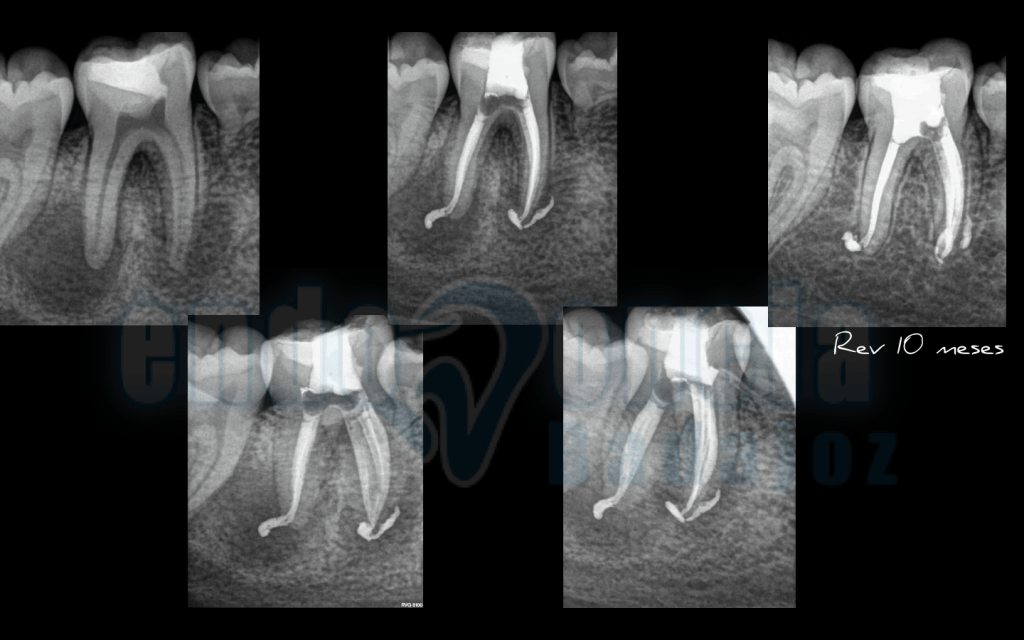

Caso 3:

Molar inferior , con una Periodontitis Apical Asintomática, con gran lesión apical, que vemos que manejando la anatomía interna y haciendo un buen tratamiento, a los 10 meses vemos una gran regeneración de la lesión.

Captura de pantalla 2015-12-08 a las 11.26.54